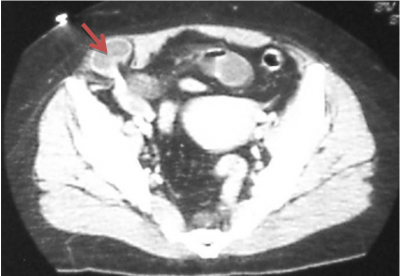

האבחנה לעתים קרובות קשה, מכיוון שהבקע פורץ בין השרירים ולא מתחת לעור, וכמו-כן הוא נוטה לכיוון לטרלי, כך שקשה להעריך את מוצאו. בקע זה נוטה להיכלא ולעבור סטרנגולציה (חנק). בדרך כלל החולים מספרים על אי-נוחות או כאבים בשיעול. לעתים הסיפור הקליני מלווה בהקאות או בבחילות ואז קשה להבדיל בין הבקע לבין מחלות תוך-בטניות אחרות. האבחנה מתבצעת על-ידי מישוש גוש בבטן במקום המתאים, שניתן להחזירו לבטן. לאחר ההחזרה ניתן למשש את הפגם בפסציה. לעיתים הבקעה מאובחן בעזרת טומוגרפיה ממוחשבת (CT) המבוצעת עקב כאבי בטן מקומיים (תצלום 2.13).